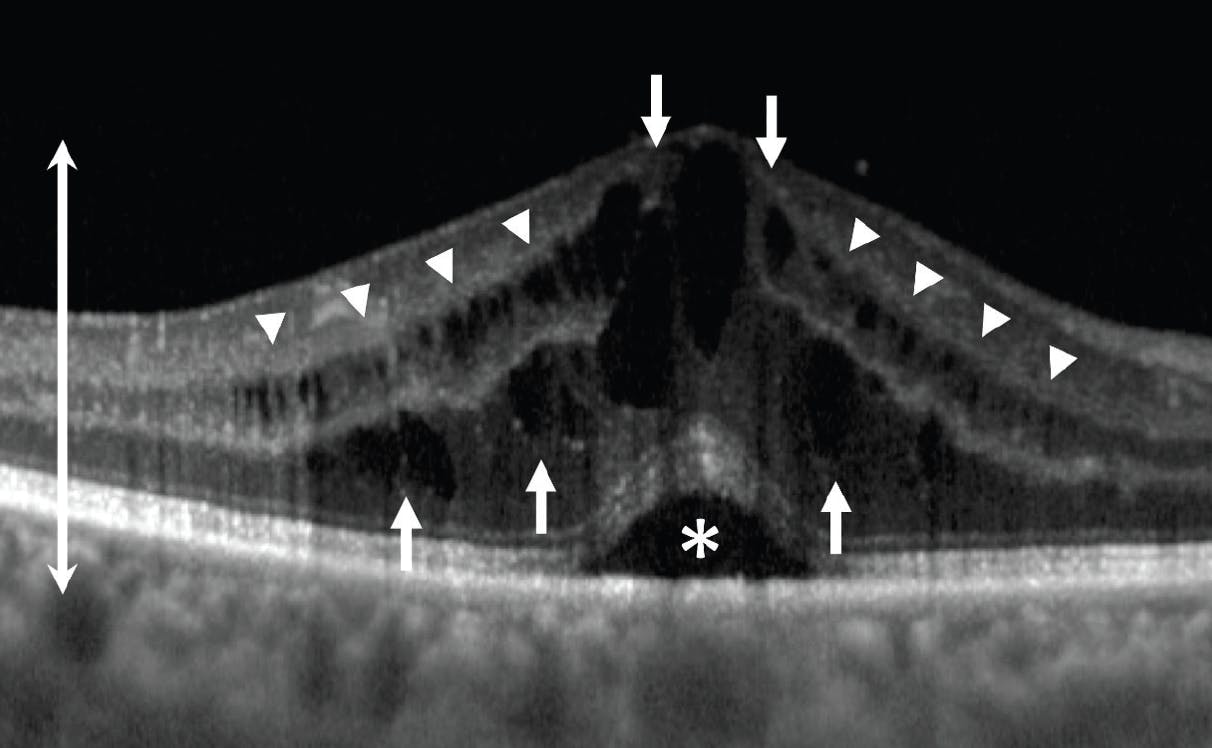

Three major patterns of ME have been described based on their OCT appearance (Figure 1).6,7 The most common pattern, cystoid ME (CME), is characterized by clearly defined, large, low-reflective intraretinal spaces.7 Diffuse ME is characterized by generalized increased retinal thickness with small, sponge-like, low-reflective spaces. Serous retinal detachment is a clean separation of the neurosensory retina from the retinal pigment epithelium.7 Correlations between each of these OCT patterns and baseline BCVA, response to treatment, and long-term visual prognosis in UME have been widely studied.8

<p>Figure 1. This OCT image demonstrates all three major patterns of ME in one unlucky patient. CME (arrows) appears as large, clearly defined, cystoid spaces. Diffuse ME (arrow heads) appears as small, sponge-like, low-reflective areas. Serous retinal detachment (asterisk) appears as a clean separation of the neurosensory retina from the retinal pigment epithelium. ME is also associated with increased central retinal thickness (double-headed arrow).</p>

Figure 1. This OCT image demonstrates all three major patterns of ME in one unlucky patient. CME (arrows) appears as large, clearly defined, cystoid spaces. Diffuse ME (arrow heads) appears as small, sponge-like, low-reflective areas. Serous retinal detachment (asterisk) appears as a clean separation of the neurosensory retina from the retinal pigment epithelium. ME is also associated with increased central retinal thickness (double-headed arrow).